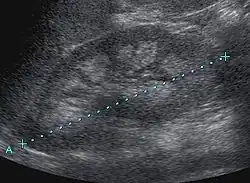

Nephrocalcinosis is diagnosed for the most part by imaging techniques. The imagings used are ultrasound (US), abdominal plain film and CT imaging.[10] Of the 3 techniques CT and US are the preferred modalities.